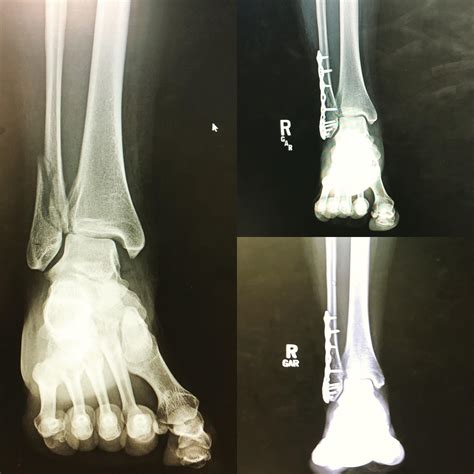

The results of your broken ankle Xray dictate your recovery plan. If the bone pieces are aligned, your doctor may suggest conservative treatment. This involves wearing a cast or specialized boot for several weeks to allow the body's natural healing process to bridge the gap in the bone.

However, if the Xray indicates that the joint surface is uneven or that the bone is severely displaced, surgery may be recommended. This is often referred to as Open Reduction Internal Fixation (ORIF), where a surgeon uses hardware like metal plates and screws to hold the bones in the correct anatomical position while they heal. Following surgery, you will likely undergo follow-up Xrays periodically to monitor bone union.